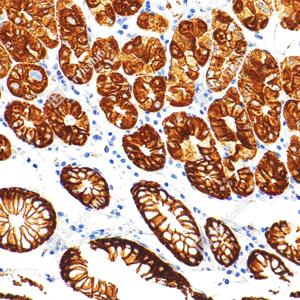

IHC检测Cytokeratin 18蛋白(货号 GB15232). 样品: 人结肠癌, 4%多聚甲醛 (货号G1101) 固定12-24小时. 抗原修复: 柠檬酸抗原修复液(干粉, pH 6.0) (G1201), 高压锅均匀喷气计时2分钟. —抗: 1: 500稀释, 4℃ 孵育过夜. 二抗: S-vision免疫组化多聚二抗(山羊抗小鼠), 即用型(货号G1301), 室温孵育20分钟. |